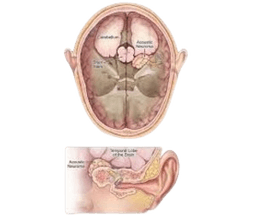

Meningioma

Meninges are the layer of tissue that protects the brain and spinal cord. A meningioma is a brain tumor that develops in meninges. Meninges are made of three layer tissues that cover and protect the brain and spinal cord. Meningiomas start from cells made up of particular arachnoid cells which are found in a thin, web-like layer that covers the brain and spinal cord. This layer is one of those layers that protects and makes up the brain's covering protective system known as meninges. -br Meningiomas in India are not always cancerous (benign), although sometimes they can be cancerous and malignant. If a tumor is cancerous it means it's aggressive or can spread out in other tissues as well or can spread in other parts of the body. A benign tumor is the type of tumor that can't spread to other parts of the body. -br Meningiomas are mostly located near the top or outer curve of the brain. They also form at the base of the skull. Spinal meningiomas are very uncommon. -br Meningiomas develop slowly and inward. They do not show any symptoms before they are diagnosed. Even benign meningiomas can grow larger enough to be life threatening if they compress and affect nearby areas of the brain.